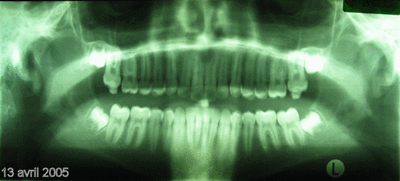

Bonjour, voici les clichés "panoramique" et "télé de profil" du 13 avril 2005 de Florent B. (voir les premiers posts pour comparer juillet 2001 et mars 2004 avec ce 13 avril 2005). J'espère que ces radios vous conviendront parfaitement pour les mesures? Aucun "trucage".

J'attends avec impatience et une grosse pointe de stress votre verdict clair, précis et concis sur l'évolution favorable ou défavorable du cas.

Ne faites pas durer le suspens trop longtemps : je n'en dors plus ! :-)